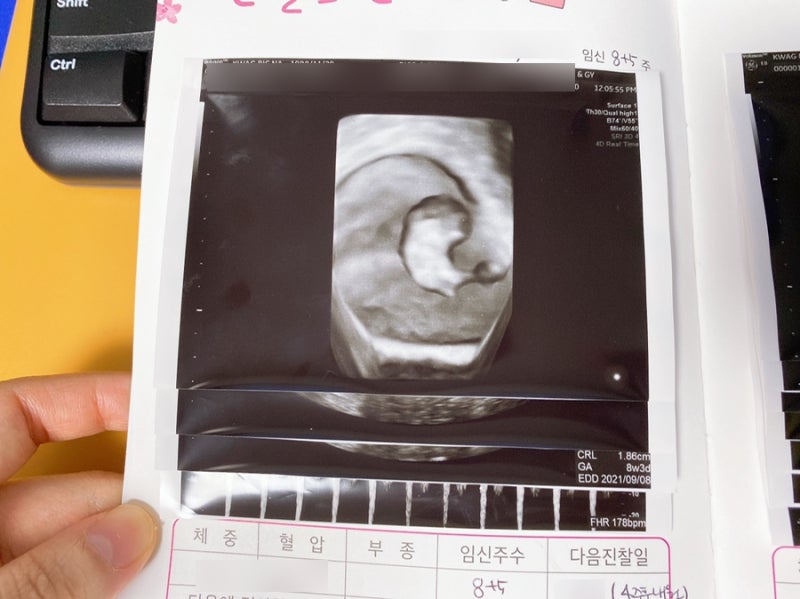

처음 임신했을 때는 증상이 별로 없어서 걱정했는데 시간이 좀 지나니 걱정이 쓸데없다는 걸 알게 되었어요. 7주차부터는 증상이 점점 심해졌고, 9주차부터 12주차까지는 증상이 매우 심하고 약간의 고통이 있었습니다. 이번 달이 최악입니다. 힘들었지만 입덧, 가슴통증, 하복부 통증, 두통 등 다양한 증상과 통증이 있었다고 계속 이야기 했습니다. 드디어 넷째 달에 다른 분들이 증상이 조금씩 좋아지고 있다고 하셨어요.

사실 임신 4개월 쯤 되면 증상이 많이 나아질 줄 알았는데 그렇지 않고 80% 정도 회복된 느낌이 들었고 가슴통증도 나았지만 나아지지도 않았습니다. 그러나 입덧은 조금 나아졌고, 내 질만으로도 내 삶이 향상되었습니다. 기분이 나아진 것 같아요. 참고로 저는 임신 17주차에 입덧이 완전히 사라졌습니다.